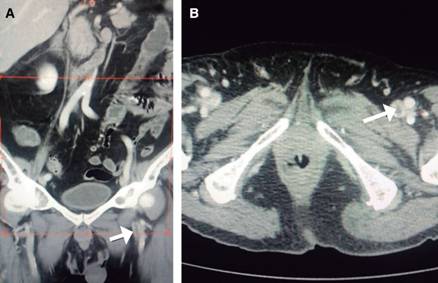

A su ingreso a urgencias, se encontró con TA 100/60 mmHg, FC 100 lpm; FR 35 r/min; oximetría de 80% al aire ambiental; cuello sin plétora yugular, campos pulmonares con estertores finos en ambas regiones infraescapulares; área precordial con ruidos cardiacos rítmicos, aumentados en frecuencia, con soplo regurgitante en mesocardio I/IV, sin irradiaciones ni galope; extremidades sin edema o signos de insuficiencia venosa superficial o profunda, pulsos y llenado capilar normales. El electrocardiograma mostró taquicardia sinusal y ondas T negativas de amplio voltaje en derivaciones precordiales V1 a V4 y en derivaciones inferiores (Figura 1). Con sospecha clínica de tromboembolia pulmonar (TEP), se solicitó dímero D, que reportó 5,000 u/L. Se estratificó al paciente en la escala de Wells modificada1 como de riesgo alto de TEP, por lo que se procedió a heparinización. El ecocardiograma transtorácico demostró dilatación importante de cavidades derechas, disfunción contráctil del ventrículo derecho y presión sistólica de la arteria pulmonar de 50 mmHg (Figura 2). Se efectuó angiotomografía pulmonar, que registró TEP submasiva con 45% de obstrucción de acuerdo al índice de Qanadli2 (Figura 3) y angiotomografía para valorar circulación venosa a nivel iliofemoral, donde se encontró trombosis venosa profunda izquierda (Figura 4). El grupo de respuesta para embolia pulmonar (PERT) decidió efectuar una trombólisis mediante sistema endovascular Eko-Sonic con acceso femoral derecho y administración de activador del plasminógeno humano recombinante/rt-PA, en infusión, utilizando una dosis de 10 mg en bolo inicial tanto en arteria pulmonar mediante el sistema mencionado como en vena iliaca mediante catéter multifenestrado intratrombo por vía percutánea con abordaje en vena poplítea ipsilateral; se prosiguió con aplicación de trombolítico a 0.5 mg/hora por 15 horas en la arteria pulmonar y vena iliaca izquierda, suspendiéndose en dicho momento por presencia de hemoptisis. La dosis total de alteplase fue de 35 mg. La evolución fue progresivamente hacia la mejoría; el ecocardiograma de control documentó disminución significativa de la presión arterial pulmonar y reducción en el tamaño de las cavidades derechas; la angiotomografía pulmonar de control demostró descenso en la carga de trombo en ambas ramas pulmonares y la vena iliaca.

Figura 4: Angiotomografía en cortes coronal (A) y axial (B) que muestra trombosis venosa profunda (flechas) iliofemoral izquierda.